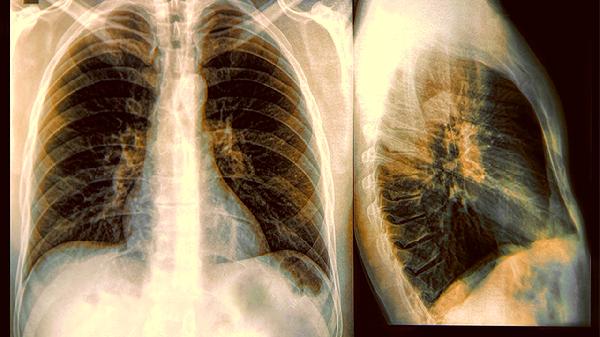

变异性哮喘是一种特殊类型的哮喘,主要表现为慢性咳嗽或胸闷症状,而非典型哮喘的喘息。变异性哮喘通常由气道高反应性、过敏原刺激、呼吸道感染、冷空气刺激、运动等因素引起,可通过肺功能检查、支气管激发试验等方式诊断。建议及时就医,在医生指导下规范治疗。